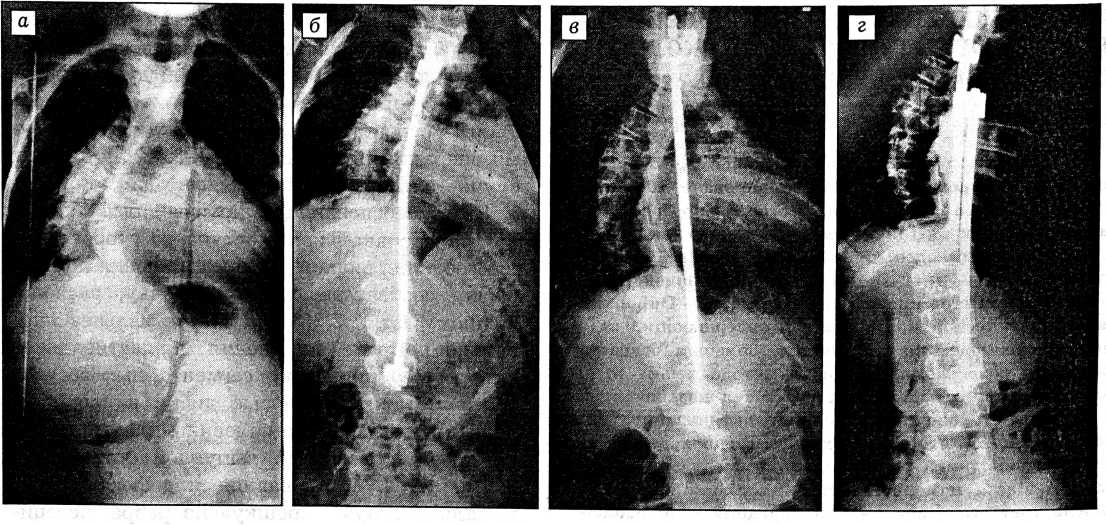

Результаты. Величина первичной сколиотической дуги, измеренная по Cobb, составила у наших больных в среднем 81° (59-108°). В результате первого этапа оперативного лечения, включавшего эпифизеоспондилодез и коррекцию дистрактором типа Харрингтона (7 больных) или CDI (3), деформация была уменьшена в среднем до 41,7°, что составило 39,3º, или 48,5%, коррекции (см. рисунок, а, б). Следует подчеркнуть, что в ходе корригирующего вмешательства мы старались не прилагать максимально возможного усилия, учитывая низкие прочностные характеристики детской костной ткани.

Второй этап коррекции проведен у 9 больных из 10, так как у одной пациентки через 6 мес после первого этапа потери коррекции не отмечено. В результате второго этапа дистракции средняя величина дуги уменьшена до 42°, иными словами, утраченная коррекция восстановлена практически полностью (см. рисунок в, г).

Рентгенограммы больной А. 7 лет с правосторонним грудным лордосколиозом IV степени. а — до лечения: величина первичной дуги 83°; б - после эпифизеоспондилодеза и коррекции сколиотической дуги дистрактором типа Харрингтона: величина дуги 40°; в- через 8 мес после двухэтапного вмешательства: смещение верхнего крюка вследствие перелома дуги позвонка, потеря коррекции до 47°; г — после замены дистрактора типа Харрингтона на CDI: коррекция деформации до 36°.